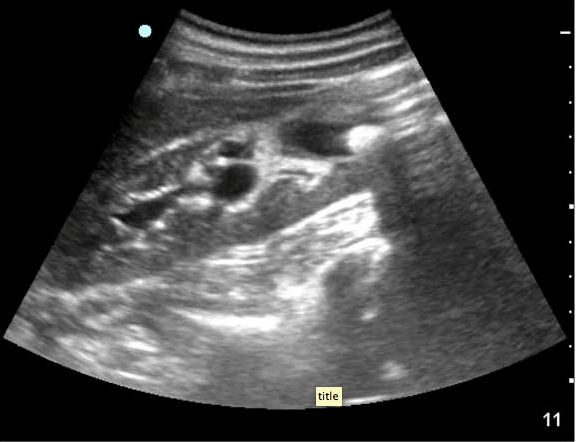

“25 yo male was found unresponsive per bystanders. Upon EMS arrival he was noted to have multiple stab wounds to the upper extremities and chest. Initial set of vitals revealed tachycardia without hypotension. Patient was intubated at the scene “for airway protection”. Mechanically ventilated upon ED arrival with the following vitals: BP 135/90 mmHg, HR 105 BPM, respirations 16/min, SpO2 100%, T 35.8 C. GCS 3T. During secondary survey found to have one stab wound to the left anterior chest (inferior to the nipple), and second stab wound to the right posterior chest (lateral to the inferior aspect of the scapula). Additional two stab wounds to both shoulders were superficial and were no longer bleeding. No apparent abdominal (wall) injuries were noted. Abdomen was non-distended and soft.

The RUQ FAST scan:

FAST ultrasound evaluation was performed after the patient was log-rolled in both directions – first to the left and then to the right.  Subsequently the patient was taken to CT scan. He remained hemodynamically stable. Below the comparative findings of FAST vs CT scans.

RUQ

perihepatic free fluid